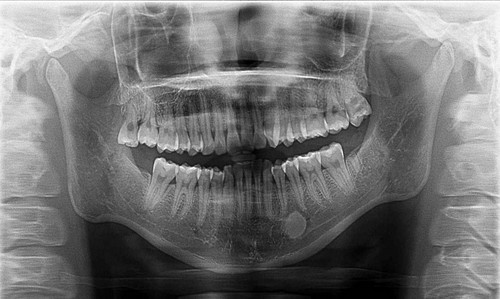

深圳口腔醫院醫生表示,口腔全景片可以用於(yu) 診斷是否有根尖炎,齲洞,囊腫,多生牙以及智齒位置等,在較的醫院才會(hui) 有配置,所以通常要到專(zhuan) 業(ye) 的正規醫院進行才好。全景片費用的話,一般在一兩(liang) 百元左右,每個(ge) 醫院設備不同,收費情況可能會(hui) 不同。

口腔全景片其實是有一個(ge) 專(zhuan) 業(ye) 的口腔全景機器,一般**穿上防輻射服,站在相應的區域,把頦部放到一個(ge) 機器上,然後機器尅圍著頭部掃描一圈,這樣就能清晰的看到口腔內(nei) 所有的牙齒的情況,就能很好的判斷有幾顆智齒,缺了幾顆牙,蛀牙情況怎麽(me) 樣,以及牙齒畸形是否嚴(yan) 重等等。但也不是所有的牙齒情況都需要拍全景片,建議聽從(cong) 專(zhuan) 業(ye) 醫生的建議比較好。